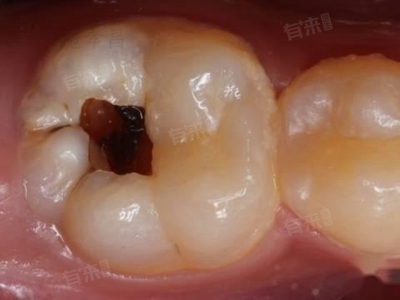

牙齿出现洞多因细菌侵蚀牙体组织,引发龋齿,若不及时处理,龋洞会逐渐加深,累及牙髓甚至根尖周组织。根据龋洞深浅和牙髓状态,需采用不同的处理方式,以恢复牙齿形态与功能,防止病情恶化。

1、龋洞填充:当龋洞较浅,尚未累及牙髓时,可采用龋洞填充的方法。医生先用专业工具去除龋洞内的腐质,彻底清除感染的牙体组织,随后对窝洞进行消毒处理。接着,选择与牙齿颜色相近、性能合适的填充材料,如树脂材料,将龋洞严密填充,恢复牙齿外形。填充后,患者需注意避免立即进食过硬、过黏食物,防止填充材料脱落。

2、护髓治疗:若龋洞较深,接近牙髓但牙髓仍处于可复性状态,为保护牙髓活力,会进行护髓治疗。先小心去除龋洞内大部分腐质,在接近牙髓的洞底覆盖具有促进修复性牙本质形成和保护牙髓作用的护髓材料,隔绝外界刺激,再用暂封材料封闭窝洞。观察一段时间后,若牙髓无异常反应,再进行永久填充,以保存牙髓,避免后续根管治疗。

3、根管治疗:当龋洞已累及牙髓,引发牙髓炎或根尖周炎时,需进行根管治疗。医生在局部麻醉下打开牙髓腔,清除感染的牙髓组织,对根管进行清理、消毒和充填。整个过程一般分多次进行,每次间隔1-2周,待炎症完全消退后,再进行永久性填充和冠修复。根管治疗能有效消除炎症,缓解疼痛,保留患牙。